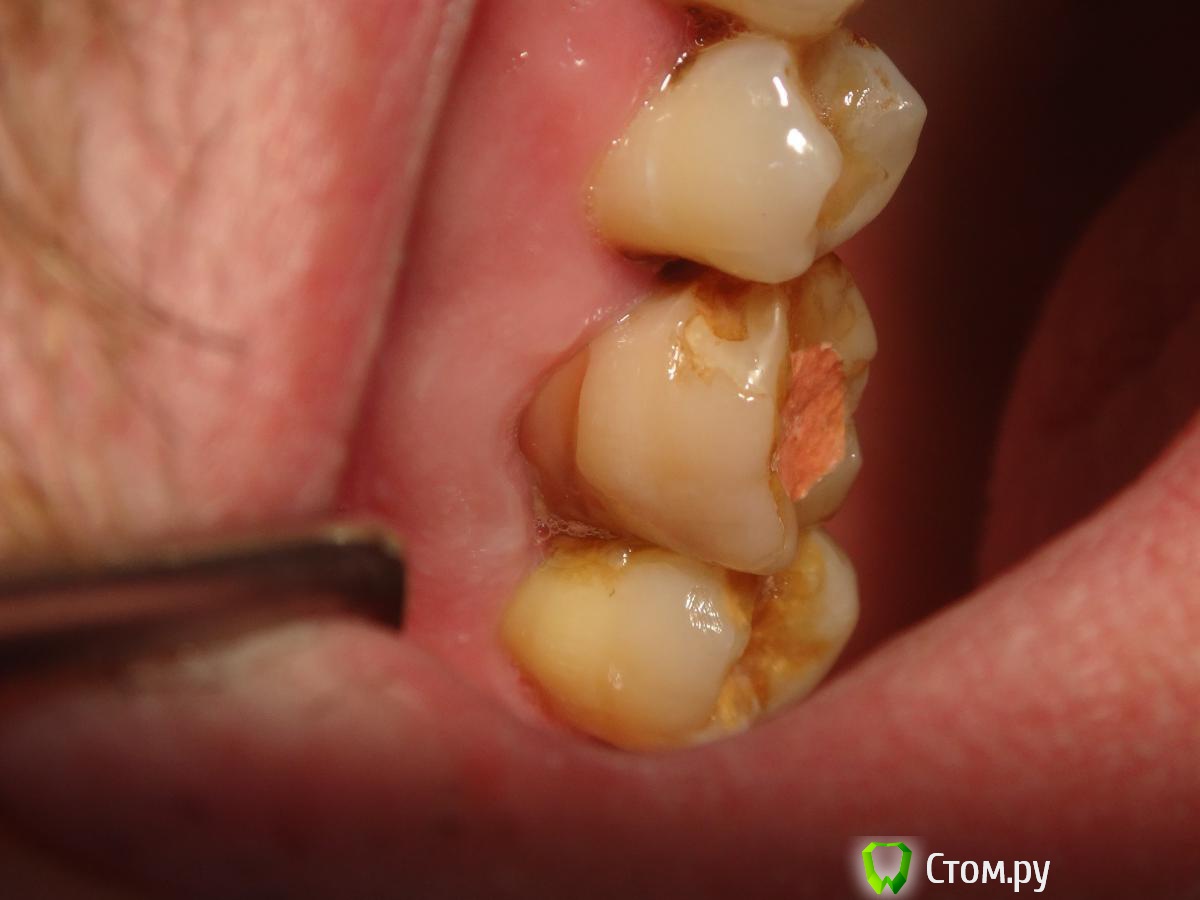

Slaggy Опубликовано 6 ноября, 2014 Автор Поделиться Опубликовано 6 ноября, 2014 Кейс некрасивый. Но какой уж есть.За качество снимков дико извиняюь. Мой рекордсмен: Пациент обратился по гарантии в клинику. 16ый зуб. Жалобы периодонтитные.снимок 2 месяца назад - Пломба поразила своей оригинальностью ((( - не суть.нашел каналы - временная пломба - Запломбировал - Шесть каналов - 3 в МВ системе, 2 в DB и небный. Вернул нашлепку на место. Обычно отправляю к доктору - виновнику торжества на пломбировку, но тут решил, что через недельку обточу и коронку, потому что МОД полость, глубоко, пломба - на снимке во всей красе. Если полностью убрать и переделать - все одно под коронку.Снимки без коффера, сделаны после снятия оптрадама. 4 Ссылка на комментарий

Slaggy Опубликовано 22 ноября, 2014 Автор Поделиться Опубликовано 22 ноября, 2014 (изменено) С "неаккуратным зубом" - откинул, заполировал, ушил, времянка. Фоткать некогда было, может на следующих этапах. Свеженькая находка 5 в шестом Кальций, тефлон, септопак - из-за недостатка времени. Снимки сам стал делать ))) пока кривенько. Изменено 22 ноября, 2014 пользователем Slaggy 2 Ссылка на комментарий